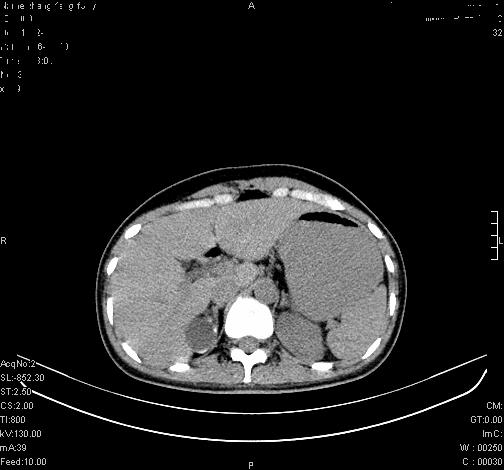

标题: CL0340:【】肾上腺囊肿,比较典型。

患者为年轻女性,查体发现右侧肾上腺囊性占位。无临床体征。

这么漂亮的图像,一看一目了然。典型的右侧肾上腺囊肿,周围有钙化。感谢搂主!

“肾上腺囊肿组织学分为4类:1)内皮细胞性,2)假性囊肿,3)寄生虫性,4)上皮细胞性。其中内皮细胞性最为常见。假性囊肿多为肾上腺内出血后遗留囊腔,囊壁无上皮细胞。寄生虫性多为包虫病引起。上皮性则很少见。”

这么明显的弧形钙化,多考虑包虫病所致的寄生虫性囊肿。

右侧肾上腺囊性密度灶囊壁有钙化。考虑肾上腺囊肿,结核?

右侧肾上腺囊肿,周围有钙化。